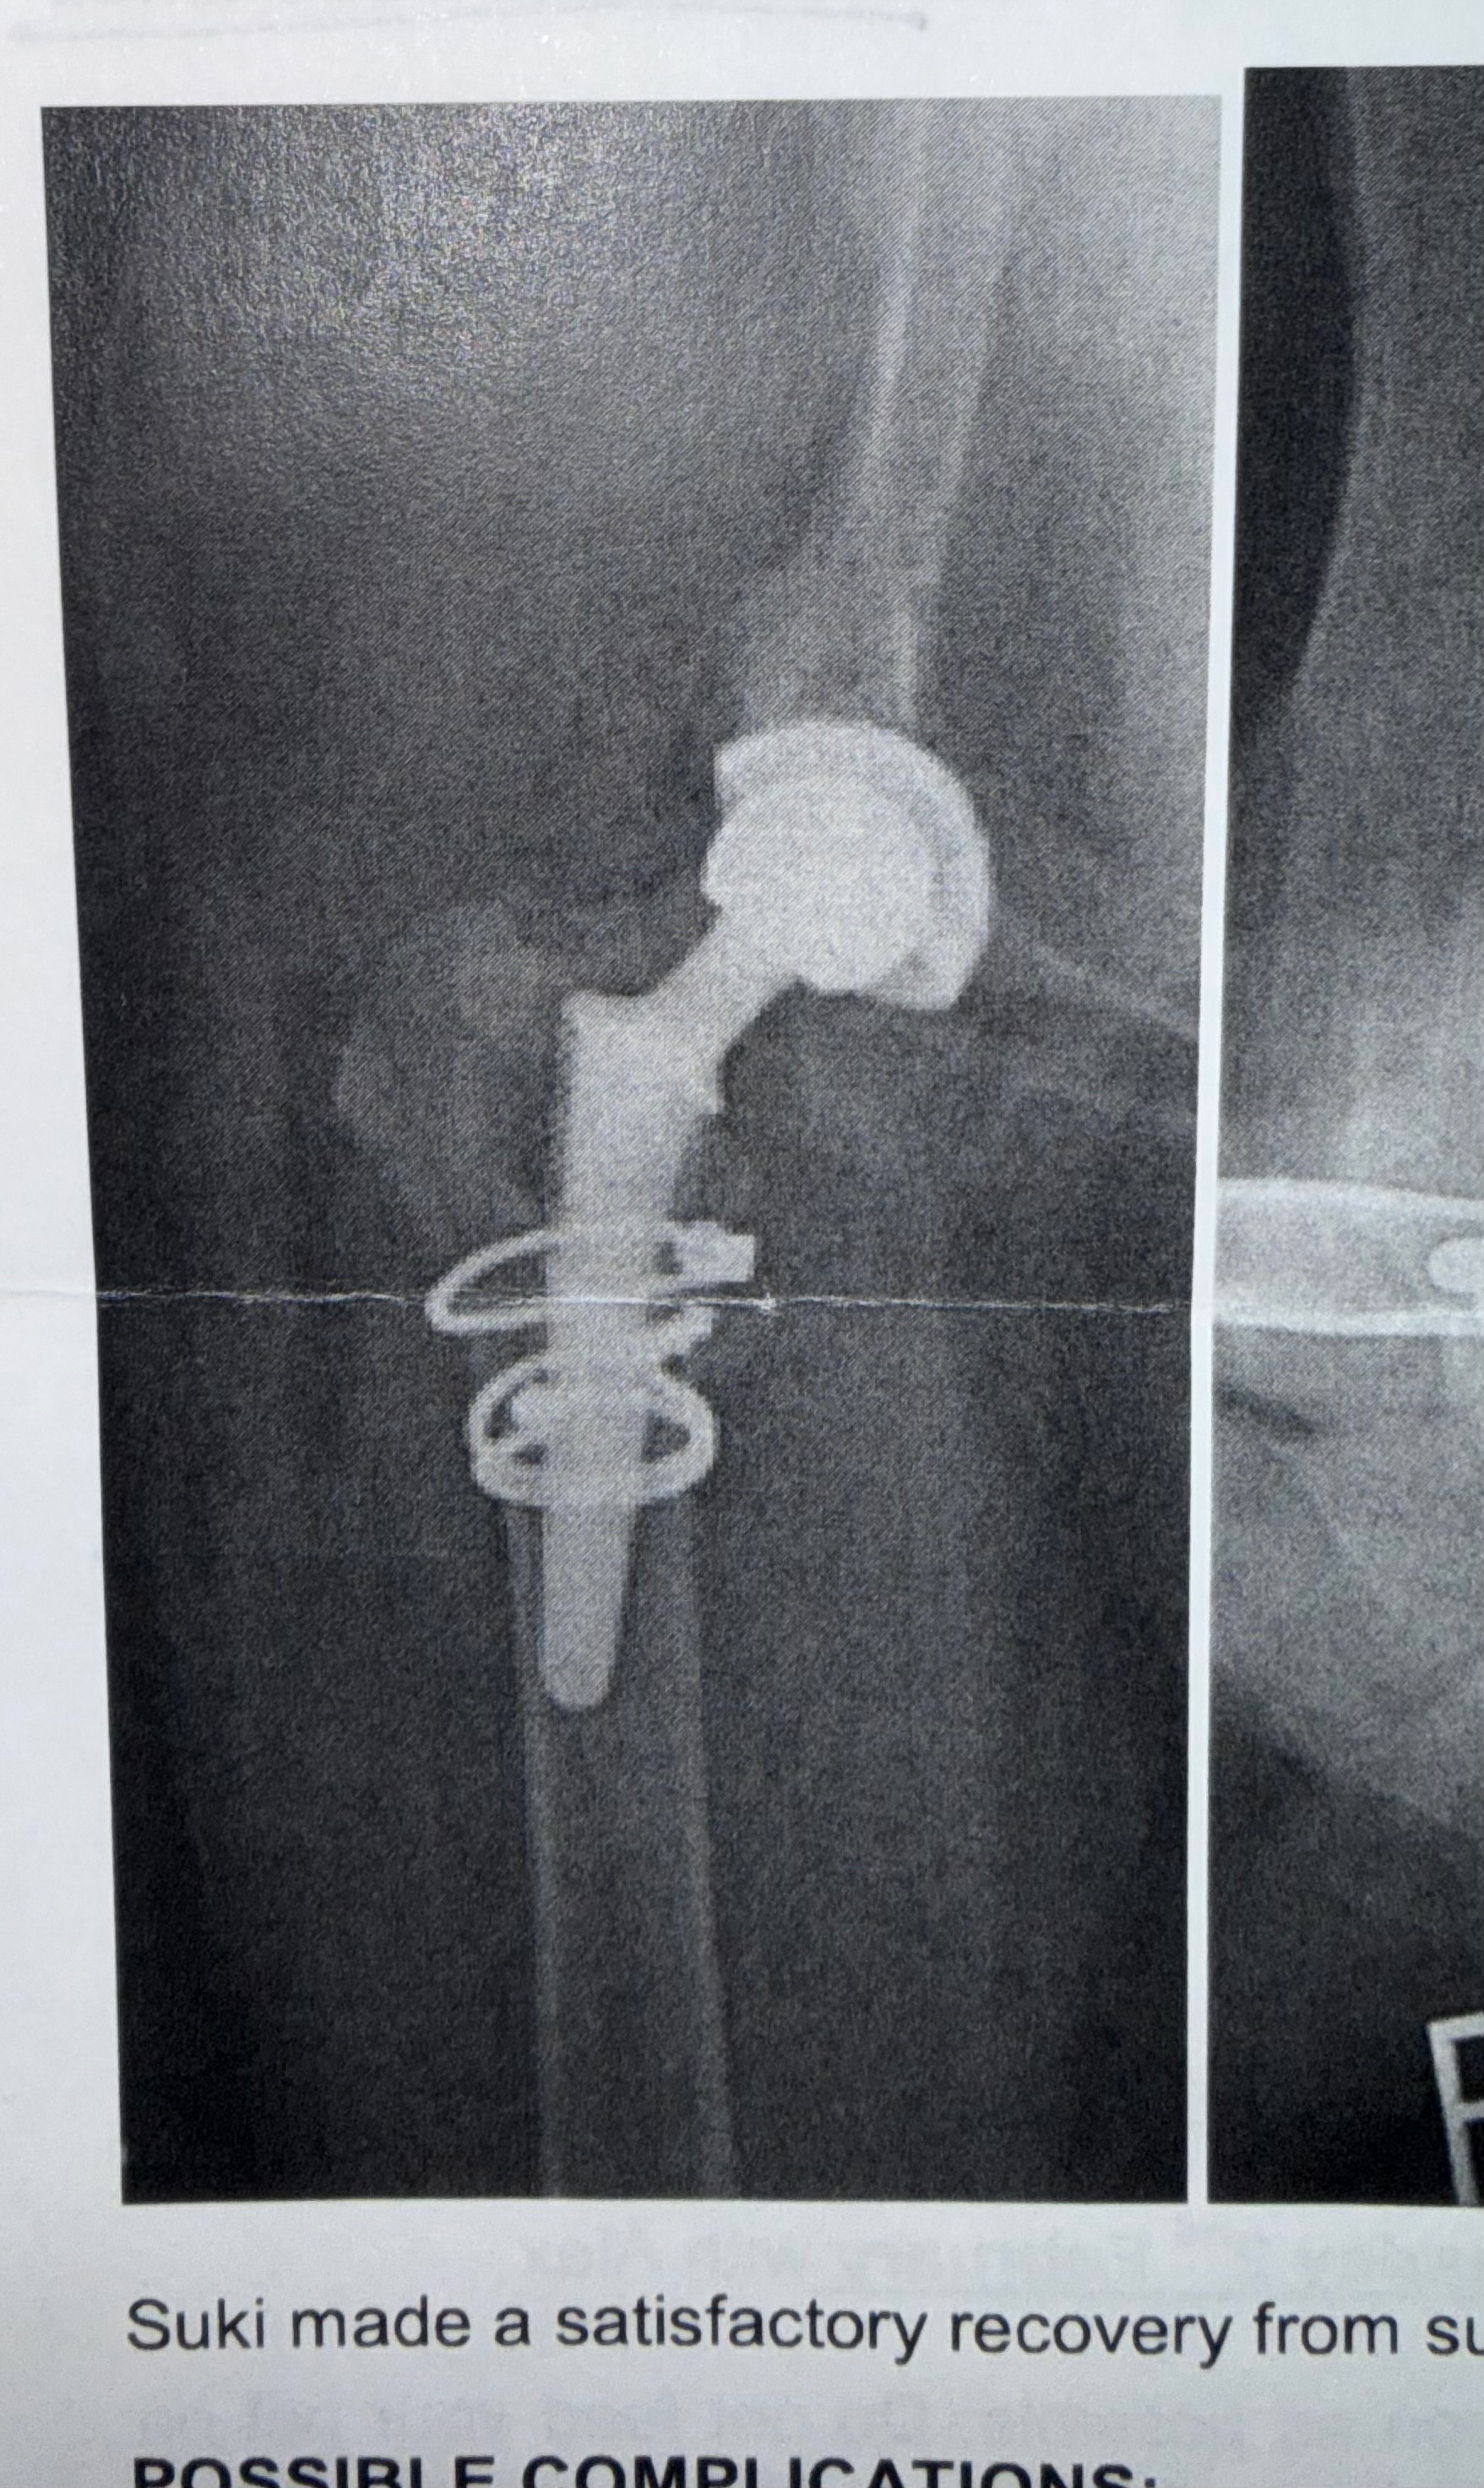

My beautiful dog Suki has severe hip dysplasia and when she was just 10 months old, she had her first total hip replacement back in 2021.

The surgery was a little more complicated than expected as her femur fractured slightly during the procedure, but she recovered incredibly well and has enjoyed the past few years living life to the fullest — running on the beach, going on long walks, and doing plenty of zoomies.

FYI - photos of the X-RAY are from before and after her 2021 surgery. I’m awaiting pictures of the CT done today and will add these once they arrive!!